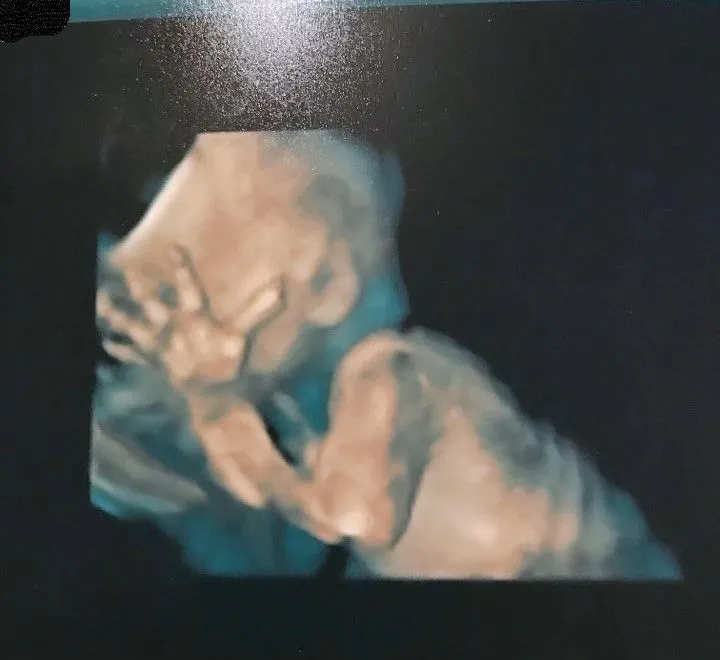

只是那天照了快2小時,真的差點快睡著。不過我運氣不錯,寶寶不但有配合動來動去可看清手指、腳趾、各部位骨頭及心臟等,負責照的女醫生也很親切,幫我拍了很多寶寶照片,之後我的主診醫生剛好也負責高層次,所以也有來幫我再照一次及拍了一些照片給我,讓我拿著很多照片離開。在照完高層次後,醫生也有在小診間再次說明每張照片的部位是什麼(只是我回家就忘記+看不懂了),整體感覺很詳細及安心,特別看到那些3D模擬照,真的很特別,也終於比較看到寶寶的樣子,不然看黑白的超音波照都覺得很難看懂臉是長什麼樣。